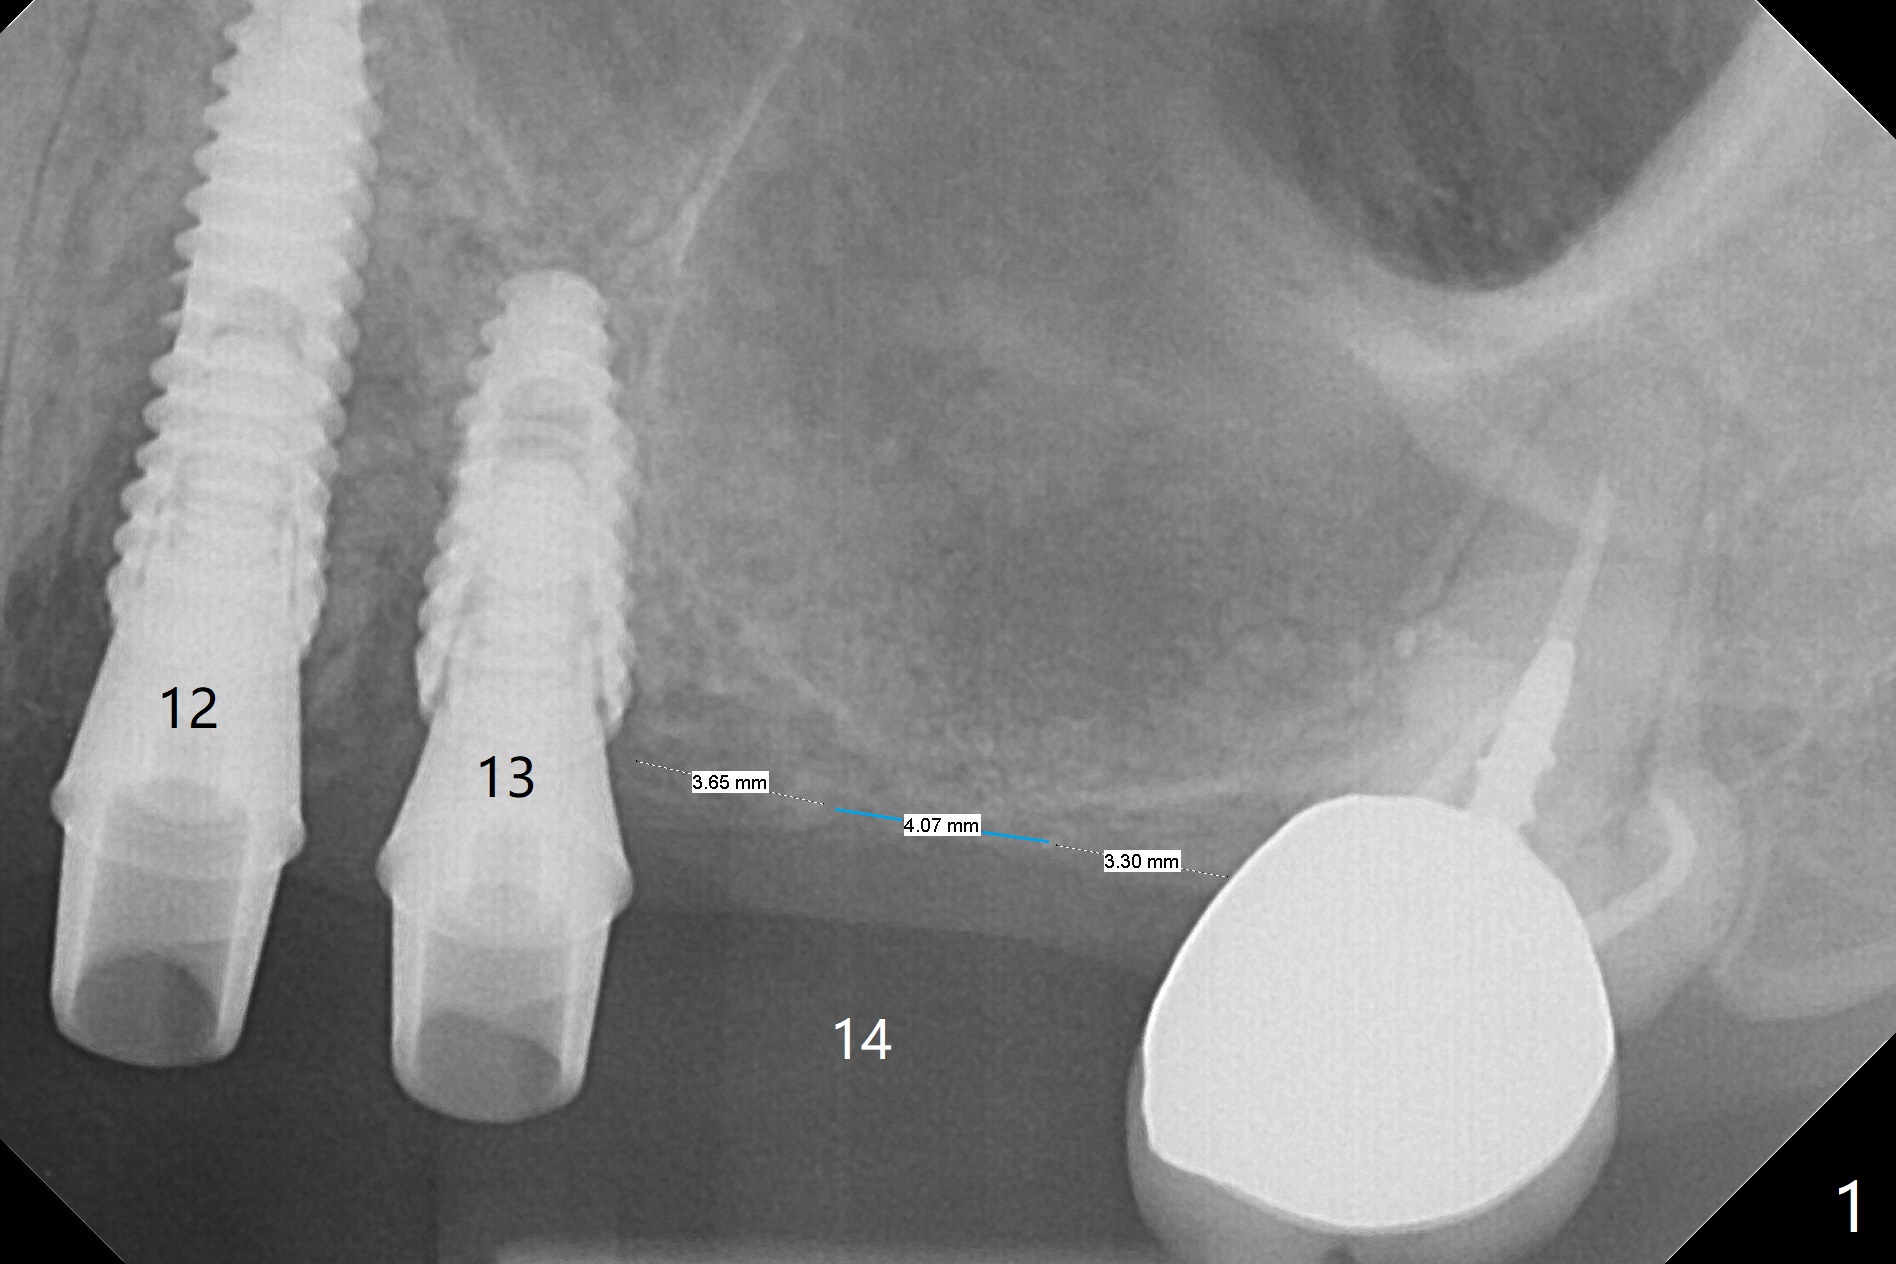

A 68-year-old timid woman is considering implant at #14 twenty months post cementation of #13 and 14 crown (Fig.1). Because of the narrow buccopalatal width (Fig.2 CT coronal section, B: buccal), a 4 mm implant (blue line) seems to be appropriate for the site (Fig.1). After crestal incision and flap reflection, a diamond round bur is used to thin the sinus floor until the bluish membrane is barely visible. An osteotome (Magic Sinus Lifter) is used for penetration. Water lift will be conducted if necessary, considering the already thickened sinus membrane (Fig.3 (CT sagittal section) M). Insert the first PRF membrane, followed by bone graft (not too sticky) repeatedly. Use sensor 1 to confirm lift degree. Try a 4x7 mm dummy FC to test stability. Place a definitive one (probably Magicore) if indicated. Use a second PRF membrane before closure of the wound. After nearly 15 month consideration (including coronovirus), the patient decides to get it done. With incision (Fig.4) and Marking Drill (Fig.5, the sinus membrane barely visible in the middle of the osteotomy (dimple, Fig.6 (black triangle)), the sinus floor does not break upon Magic Sinus Lifter). Later the patient complains of discomfort with tapping. In fact Magic Drill (similar to trephine bur, Fig.7) is used to break into the sinus without membrane perforation (Fig.8). Remember the thick membrane (Fig.2,3). In fact the fractured fragment is attached to the membrane (Fig.9 red lines, green sticky fracture). A small curette is used to further separate the membrane from the bony wall (Fig.10) before insertion of a small piece of PRF and sticky bone. When a 4.5x7 mm dummy implant is incompletely placed with stability (<10 Ncm), the membrane is stretched over the bone graft (Fig.11 M). After removal of the dummy, the major remaining piece of PRF (from 9 cc vial) and more allograft are placed before inserting a definitive implant (same size) with 15 Ncm; still the used to be thick membrane remains intact and stretched (Fig.12 M). The implant is equicrestal buccal, while slightly supracrestal palatal. To prevent implant dislodgement into the sinus and bone graft, a final abutment is placed (Fig.12). The wound is closed with 4-0 PGA, perio glue and perio dressing. The latter dislodges 3 days postop. The wound seems to be healing. No dressing is reapplied.